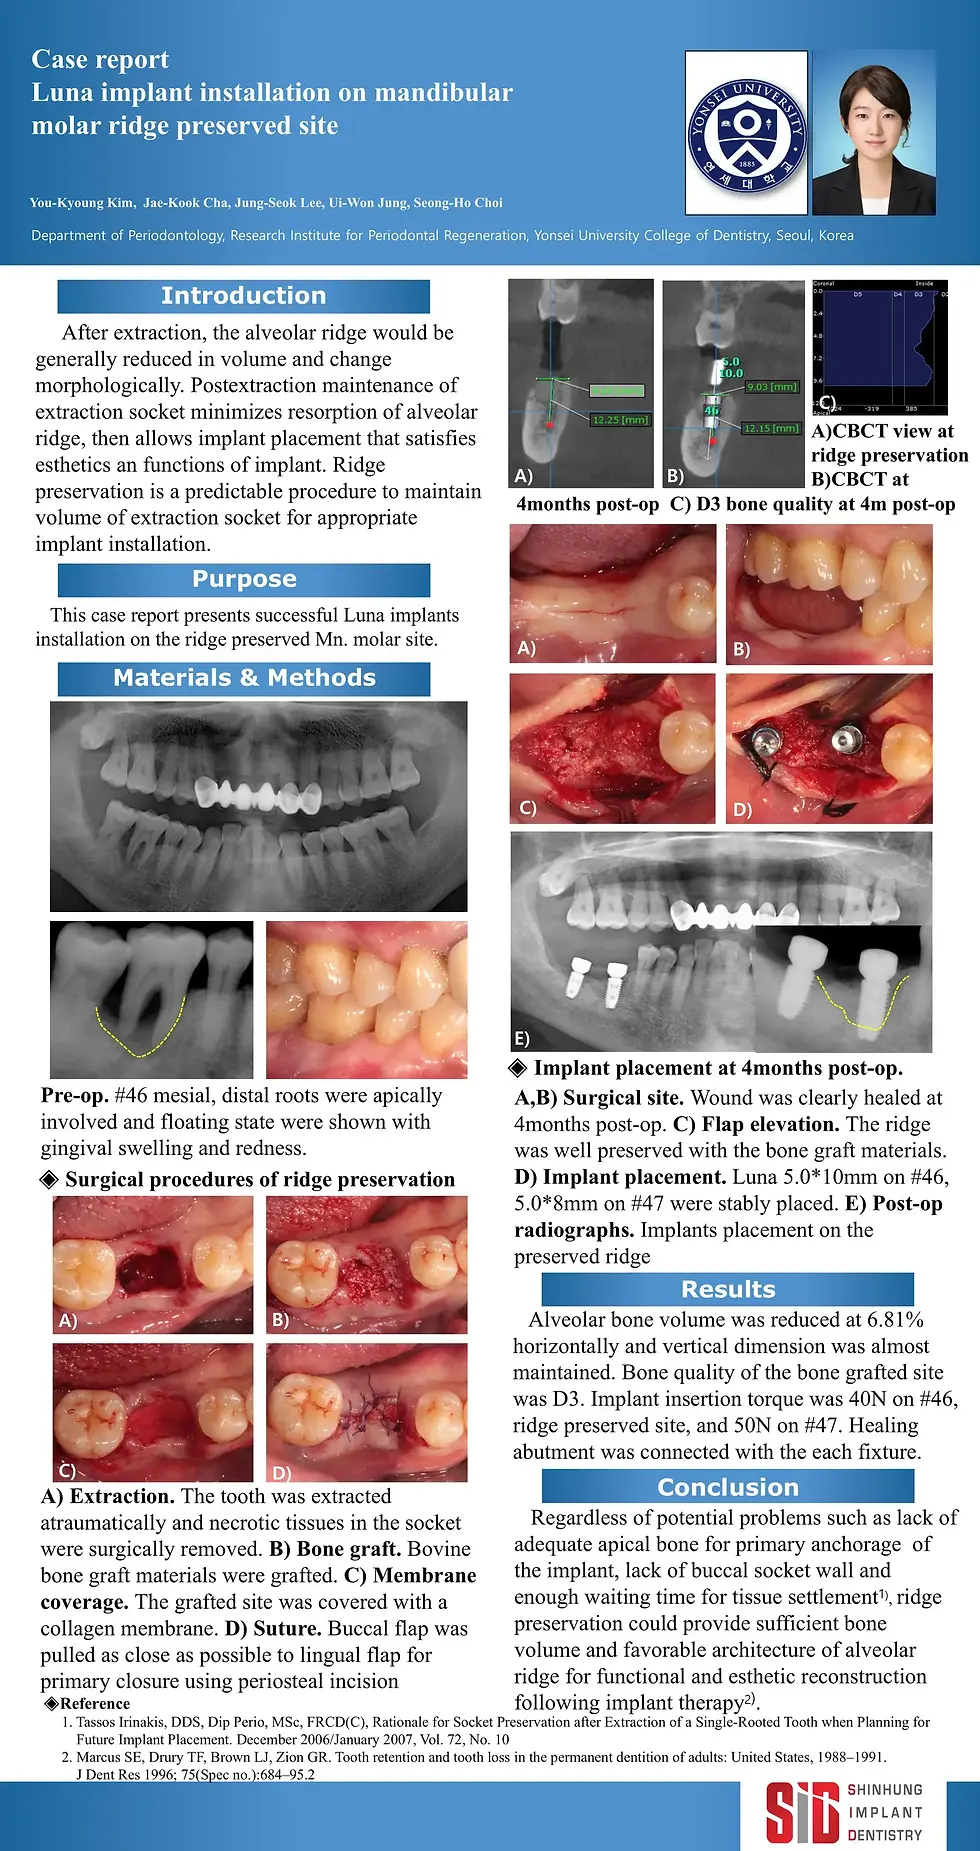

2016 poster